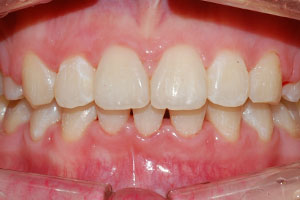

치료증례 전후사진

Before & After